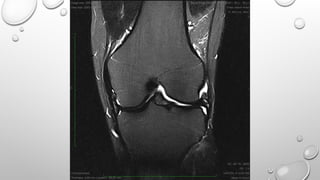

• THEY ARE GENERALLY USED TO CREATE T2* WEIGHTING IMAGES IN VERY SHORT SCAN TIME

THEY ARE USED IN

• MR ANGIOGRAPHY

• MR MYELOGRAPHY

• SWI

• MENISCAL AND CARTILAGE MAPPING

DISADAVANATGE : SENSITIVE TO FLOW AND MOTION